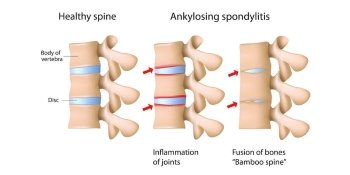

Beyond the Pain: Lifеstylе Changes for Spondylosis Well-Being in Bangalore

In the dynamic landscape of Bangalore, a city that embodies the rush of modernity while cherishing age old traditions, the challenge of managing spondylosis, a widespread spinal ailment, has become increasingly prevalent. Amidst this urban hustle, where traditional healing and continuous lifestyles intersect, a holistic approach to wellness is gaining traction. This approach recognises that, […]